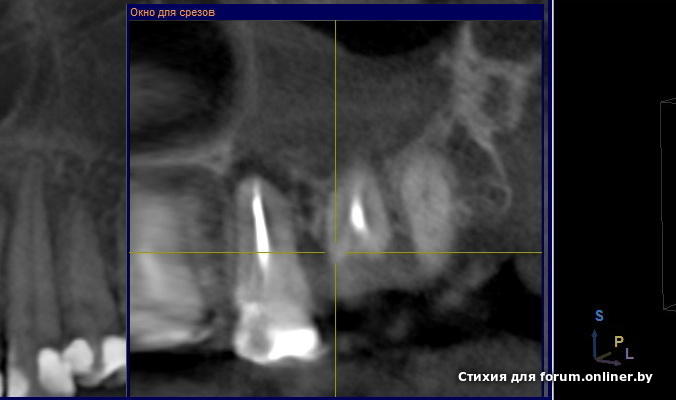

Уважаемые стоматологи! Очень прошу совета по поводу 26 зуба. Стоит ли пытаться его лечить или все-таки удалять. Десна над зубом воспалилась. Имеются пародонтальные карманы, особенно со стороны семерки. Выкладываю имеющиеся снимки (прицельные и КТ).

Tatsianka_M, вы считаете, что зубик можно спасти? Ответьте пожалуйста, я очень переживаю за этот зуб, очень хотелось бы сохранить. Каким образом можно попытаться его вылечить? Распломбировать каналы (они запломбированы год назад гуттаперчей, думаю их реально пройти) и заложить лечебную пасту? Или все-таки делать рассечение десны под больным зубом для выхода гноя и ставить дренаж? То, что у меня там пародонтальные карманы, не будет ли это причиной повторного воспаления зубика через короткий срок? И вообще: откуда гранулема могла появится? Зуб лечила год назад и по снимках каналы неплохо запломбированы... Гайморит у меня хронический, не знаю, в данном случае то ли он от зуба, то ли зуб от гайморита... Очень прошу помощи, посоветуйте, стоит ли тратить деньги и время на этот зуб, чтобы спасти или он безнадежен совсем...

По поводу 5го - терапевт не догадался, что находится не в канале, а по пути вкладки - ничего сложного не вижу в прохождении этого канала, а вот предыдущий ортопед вкладок боялся как огня. По этому короткая и не по каналу.

По поводу 6ки - прогноз по измненениям на верхушке 50/50, по поводу пародонтального кармана - нужно зондировать, смотреть очно.